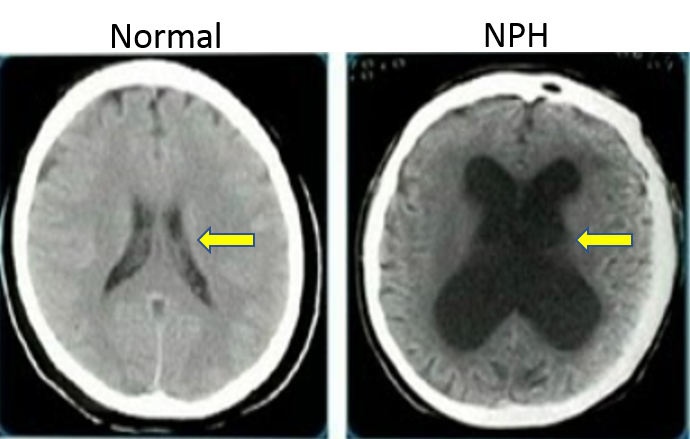

Research by Mark Johnson Provides Insights into Origins of Idiopathic Normal Pressure Hydrocephalus

New Research Grant to Study Normal Pressure Hydrocephalus